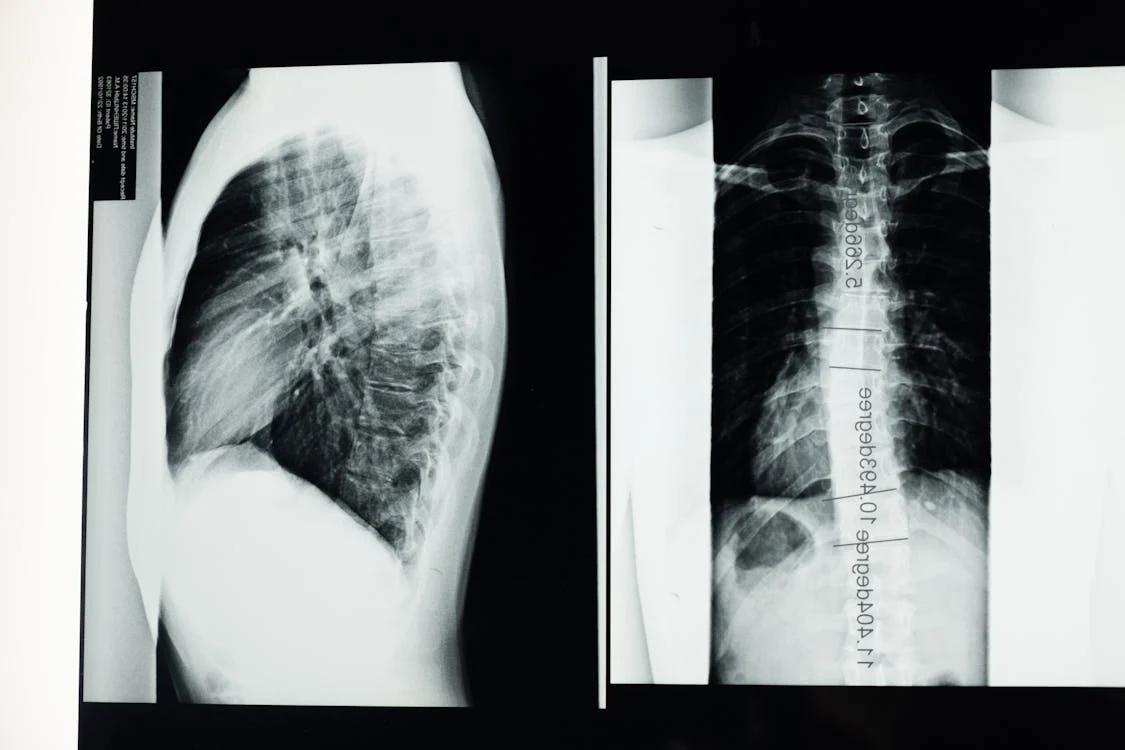

Imaging That Confirms Lung Spread

A chest CT scan is the gold standard; it can spot tiny nodules that Xrays miss. In certain cases, a PET scan helps determine whether those nodules are active cancer cells. According to , PET scans are especially useful when disease is suspected but CT results are ambiguous.